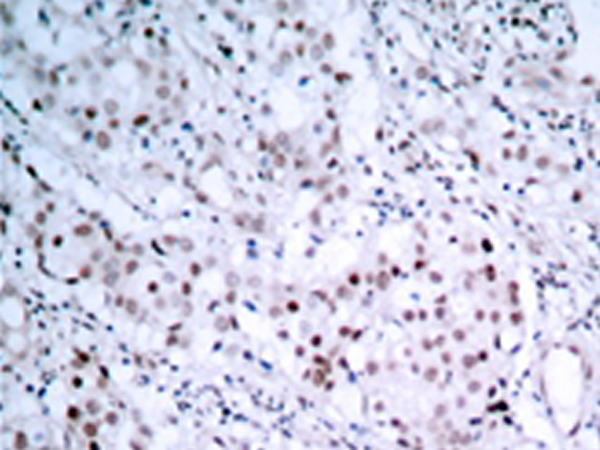

IHC positive control: |

Human breast carcinoma tissue |

IHC Recommend dilution: |

50-100 |